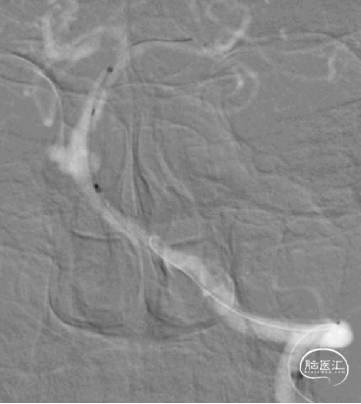

Tubridge血流导向密网支架释放,回拉定位,逐步推挤释放支架。

4

释放完毕后跟进支架导管,回收输送导丝,微导丝成袢行支架内按摩。